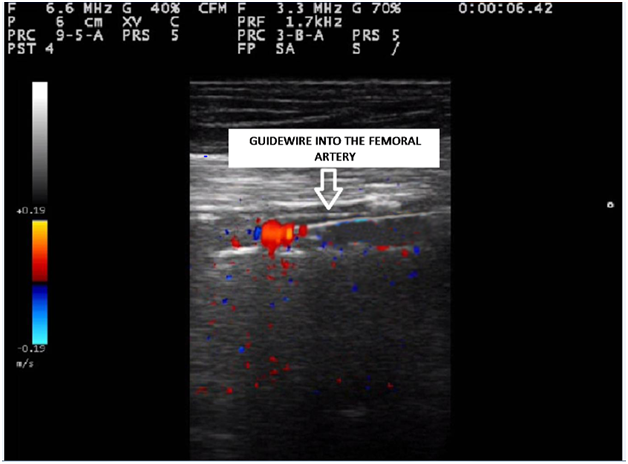

A local anesthesia (1% lidocaine) was performed at the right groin. A 7.5MHz probe of a Esaote Mylab 50-X Vision allowed the correct visualization of the common femoral artery for an ipsilateral antegrade percutaneous approach with a 5Fr sheath. A bolus of 2500IU of unfractionated heparin was administered intra-arterially to have an activated clotting time of more than 200seconds, then an hydrophilic. 035 inch guide wire with J tip (Terumo) and a directional 5Fr angle tapered directional catheter (Berenstein) were successfully advanced throughout the occlusion (Figure 2) and towards the infrapopliteal segment in the correct lumen, under the direct echographic visualization. The diameter of the SFA at the target lesion was measured and a 4x80mm over-the-wire balloon (Evercross, Covidien) was chosen for dilatation. Duplex control showed the complete resolution of the occlusion from the morphological point of view, without any sign of dissection or recoil and with normalization of both the peak systolic velocity (PSV) and the PSV ratio. Moreover, a direct bi-phasic flow was recorded on the pedal artery. No stent was needed. Postoperative course was uneventful and the patient was discharged on 2nd postoperative day on acetyl salicylic acid 100mg/daily. At 1-yearfollow-up the patient was still asymptomatic and a duplex ultrasound showed neither recurrent nor residual stenosis.

Figure 2 The hydrophilic .035 inches guide wire with J tip (Terumo) advanced throughout the occlusion in the correct lumen.